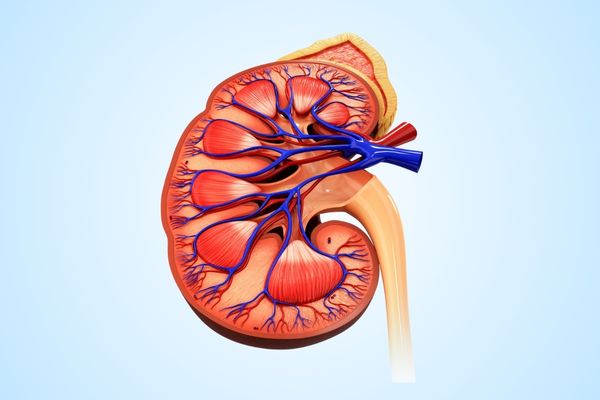

Advancing Urological Oncology: Successful Laparoscopic Nephrectomy

we are committed to offering state-of-the-art care for urological malignancies. Recently, I had the privilege of performing a laparoscopic radical nephrectomy on a 60-year-old lady with a large renal mass.

💡 Highlights of the case:

✅ Minimal blood loss during surgery.

✅ Smooth recovery—patient discharged without complications.

✅ Histopathology revealed clear cell RCC, with negative margins, ensuring she is now cancer-free.

This case underscores the efficacy of minimally invasive techniques, such as laparoscopic and robotic surgery, in managing urological cancers. These approaches offer:

🔹 Reduced postoperative pain and faster recovery.

🔹 Precision in cancer removal with excellent oncological outcomes.

🔹 Enhanced quality of life for patients.

We are proud to provide cutting-edge technology and expertise to ensure optimal outcomes for our patients battling urological malignancies.